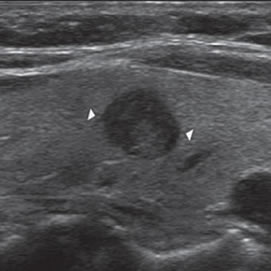

Un nódulo coloideo mixto puede aparecer como un quiste con un nódulo mural isoecogénico, excéntrico, que protruye hacia el lumen simulando una formación papilar, habitualmente vascularizado, que no corresponde a tejido neoplásico (Figura 19a). Si el componente sólido está rodeado por fluido, separado de la pared, y además tiene focos hiperecogénicos, es más difícil confundirlo con un tumor quístico (Figura 19b y c).

Figura 19. a) Nódulo coloideo, que muestra

una proyección de aspecto papilar hacia

el lumen, que corresponde a tejido no

neoplásico, igualmente vascularizado que

el resto del componente sólido del nódulo

(flecha abierta); b) y c) Nódulo coloideo,

predominantemente quístico, con componente

sólido (flecha), que muestra una forma

vegetante completamente rodeada de

coloide, con dos focos puntiformes en el

área más central.